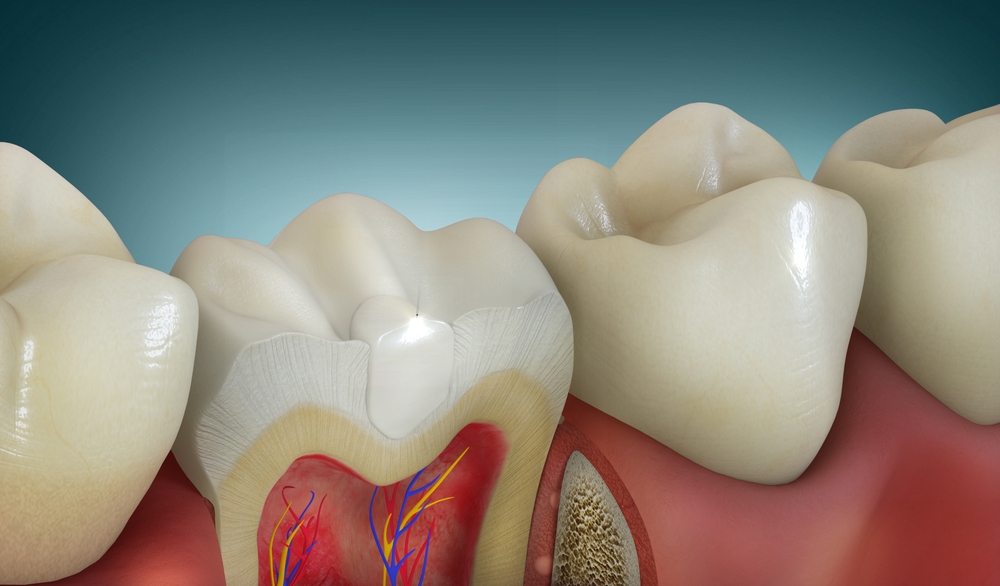

치아 내부 구조는 한 번 변화가 생기면

스스로 회복되기 어렵기 때문에,

현재 상태를 정확히

파악하는 것이 우선입니다.

충치가 초기에 머물러 있을 때는

표면 관리만으로도 충분히

정리할 수 있지만,

깊어진 경우에는 치아

중심부까지 영향을 줄 수 있어요.

중심부까지 변화가 진행되면

치아 내부까지 정리가 필요한 상황이라면

여러 단계를 나누어 진행하게 됩니다.

내부를 먼저 확인한 뒤 문제가 되는

부분을 정리하고,

그다음 치아가 다시 버틸 수 있도록

공간을 채우는 방식으로 이어집니다.